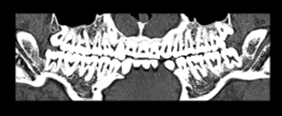

歯科解析ソフト

歯列弓に沿ったパノラマ像やクロスカット像を作成します。CTにて上顎、下顎骨の状態、神経の位置、根尖情報などの把握が可能です。また、画像に対して距離・角度の計測も可能となります。